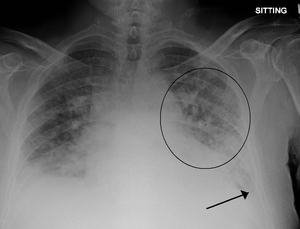

- CXR

- Cephalization

- Interstitial edema

- Pulmonary venous congestion

- Pleural effusion

- Alveolar edema

- Cardiomegaly